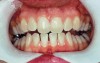

The whitening agents are available in various concentrations ranging from 10% carbamide peroxide (equal to 3.4% hydrogen peroxide) to 38% hydrogen peroxide. If the higher concentration agents contact the soft tissues, they can produce a chemical “burn” that turns the tissues temporarily white (Figure 1 and Figure 2). Although tissues quickly return to their normal color once they rehydrate, they may be mildly uncomfortable for a few hours. The patient may be distressed by the temporary appearance of the whitened soft tissues. A rubber dam or other protective barrier is mandatory to effectively seal off the tissues (Figure 3). In-office systems usually supply a light-cured resin in a syringe to apply around the cervical areas to confine the agent to the teeth (Figure 4 and Figure 5). In addition, flexible spreaders should be placed in the mouth to prevent the cheeks or lips from contacting the whitening agent.

Figure 1  Soft-tissue chemical burns near the left commissure of the mouth and along the free gingival margin due to exposure to the whitening agent.

Figure 2  Soft-tissue chemical burns near the left commissure of the mouth and along the free gingival margin due to exposure to the whitening agent.